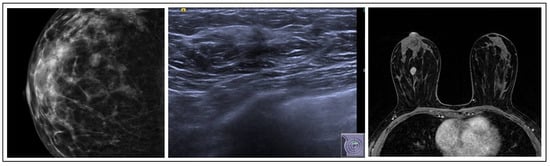

LN is typically not detectable on mammograms and is often an unexpected finding during biopsies. It usually presents as a non-palpable, inconspicuous lesion. However, in rare instances, it may be associated with microcalcifications in mammograms and occasionally as a mass or focal area of non-mass enhancement on MRI [36] (Figure 5). Classical LN appears as a low- to intermediate-grade, uniform, intralobular epithelial proliferation of non-cohesive cells, often with prominent intracytoplasmic lumina. A B3 lesion is a non-obligate precursor to breast cancer, classified by the WHO into atypical lobular hyperplasia (ALH) and lobular carcinoma in situ (LCIS). Non-classical LN types, like pleomorphic, apocrine, or florid LCIS, are B5a lesions that necessitate different management due to a higher risk of progression [28].

Figure 5. LN radiological features.